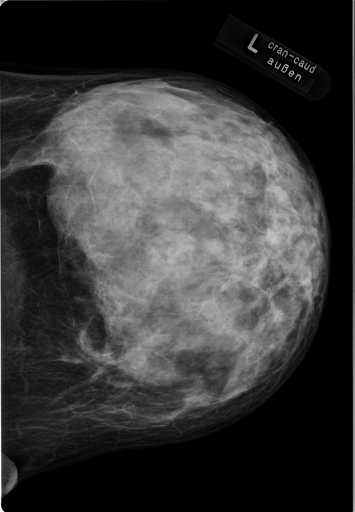

Details of the IRMA database is described in literature [24],[27],[25]. IRMA dataset offers 12,677 images for training and 1,733 images for testing. Figure 4 shows some sample images from the dataset long with their IRMA code in the format TTTT-DDD-AAA-BBB.